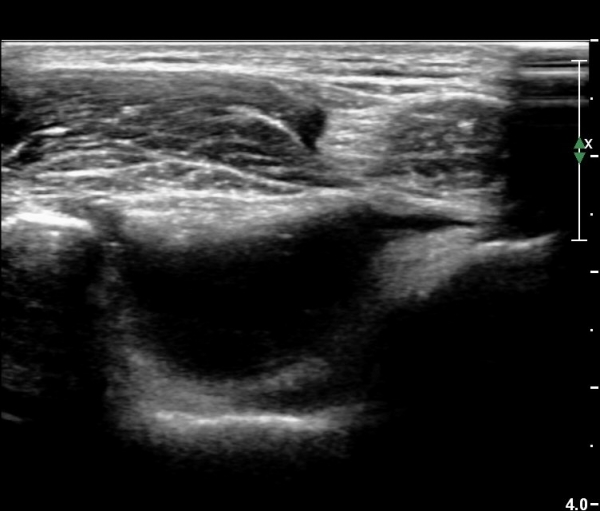

ÃÊÀ½ÆÄ °Ë»ç

ÆÈ²ÞÄ¡ ¾ÕÂÊ ¼ÒµÎ Á¾´Ü¸é°Ë»ç¿Í Ⱦ´Ü